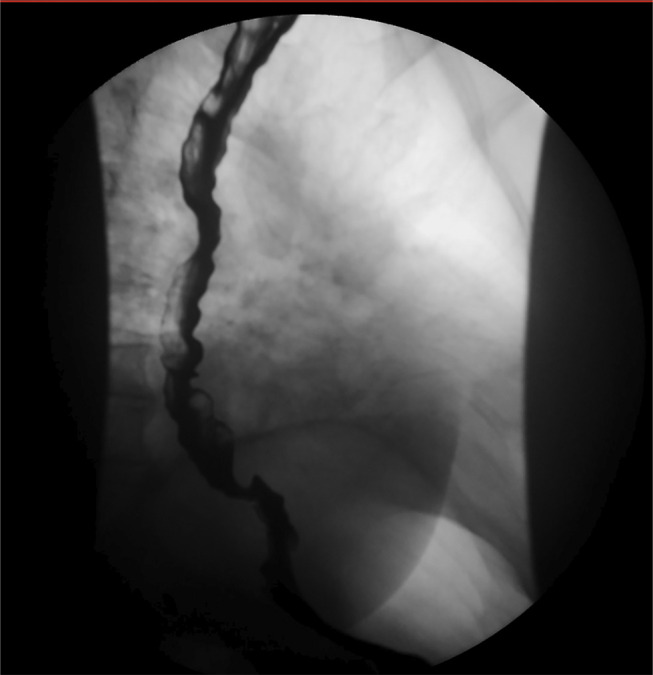

Where the Jackhammer Meets the Corkscrew: A Case of Manometric Hypercontractile Esophagus and Esophagogastric Junction Outflow Obstruction With Endoscopic Features of Distal Esophageal Spasm.